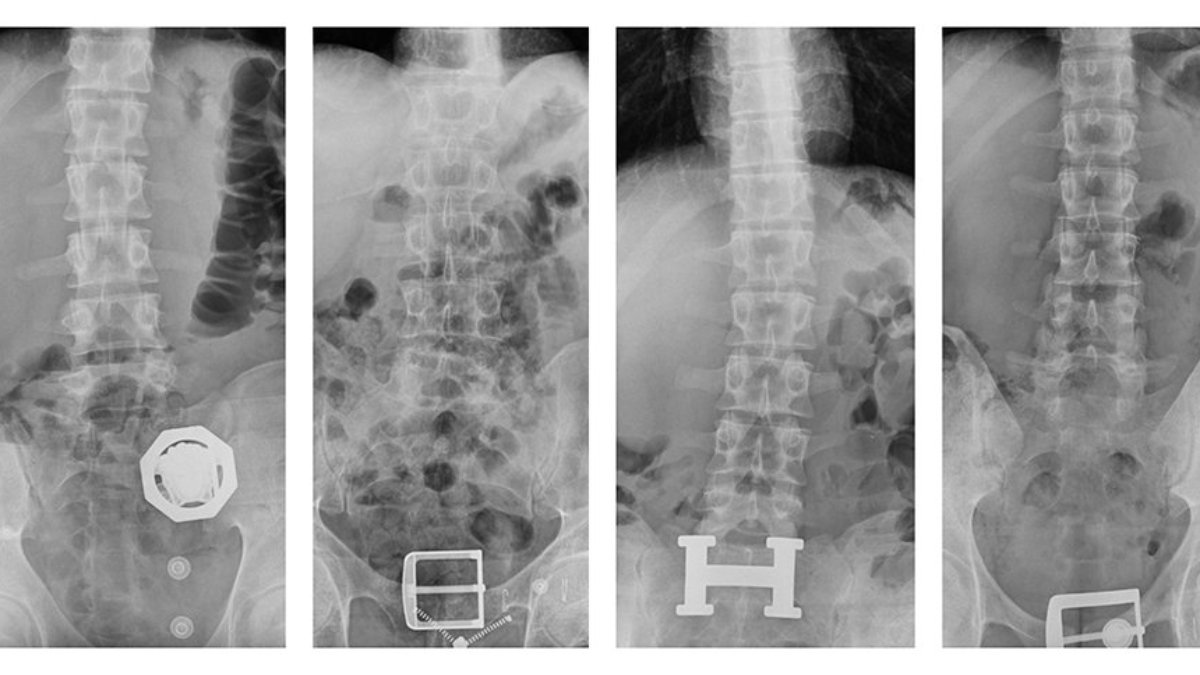

Zanlılardan birinin rahatsızlık belirtisi göstermesi üzerine polisler ellerindeki nöbetçi sulh ceza hakimliği kararıyla zanlıları doktor raporu almak üzere hastaneye götürdü. Burada zanlılardan birinin röntgen filmi çekilince şaşkınlık yaratan gerçek açığa çıktı. Röntgen filminde, yakalanan zanlının midesine cerrahi yöntemle yerleştirilmiş bir kapsül olduğu tespit edildi.

Zanlının midesinden doğal yollarla çıkan kapsülde 121 parça halinde 840 gram saf eroin ele geçirildi. Adliye’ye sevk edilen 4 zanlı burada yapılan sorgulamalarının ardından 'Uyuşturucu veya uyarıcı madde ticareti yapma veya sağlama' suçundan tutuklandı.

Diyarbakır'da, bir otomobildeki 4 şüphelinin midelerinde 121 parça halinde 840 gram eroin tespit edildi. Uyuşturucu çıkarılırken, 4 şüpheli tutuklandı.